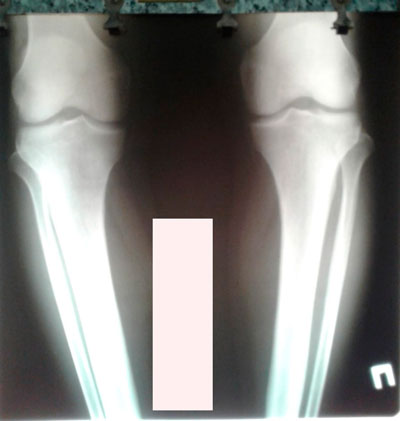

Исходник - 40 лет.

Дата операции - 22.06.2019г.

Дата операции - 22.06.2019.

Дата снятия аппаратов - 28.09.2019.

Срок лечения - 95 дней.